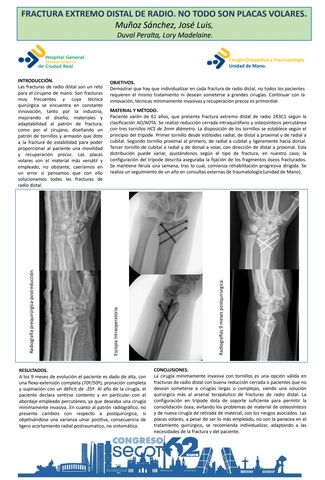

FRACTURA EXTREMO DISTAL DE RADIO. NO TODO SON PLACAS VOLARES

JOSE LUIS MUÑOZ SANCHEZ, LORY MADELAINE DUVAL PERALTA